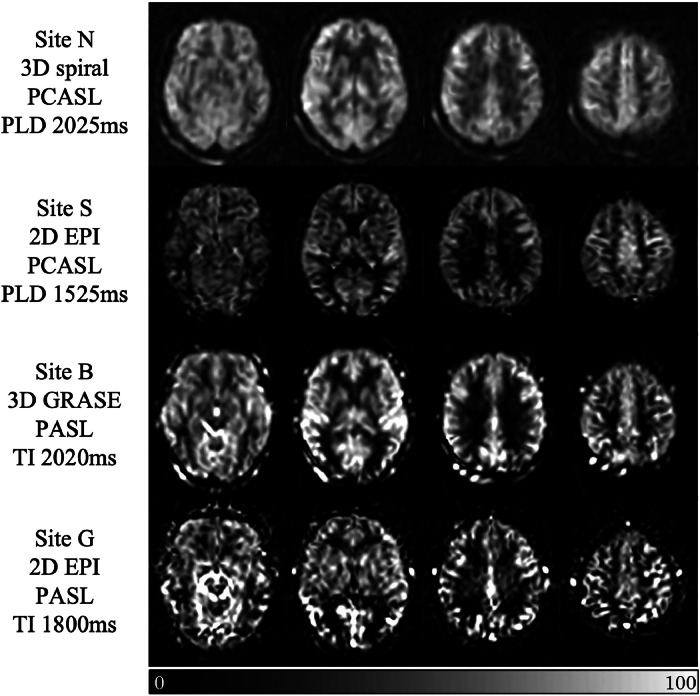

Arterial spin labelling (ASL) enables non-invasive quantification of regional brain perfusion using MRI. ASL was used in the Reducing Pathology in Alzheimer's Disease through Angiotensin TaRgeting (RADAR) multi-centre trial to pilot the assessment of the effects of the anti-hypertension drug losartan on cerebral blood flow (CBF). In the multi-centre setting, disparities in ASL implementation on scanners from different manufacturers lead to inherent differences in measured CBF and its associated parameters (e.g. spatial coefficient of variation (sCoV) of CBF, a proxy of arterial arrival times). In addition, differences in ASL acquisition parameter settings can also affect the measured quantitative perfusion values. In this study, we used data from the RADAR cohort as a case study to evaluate the site-dependent systematic differences of CBF and sCoV, and show that variations in the readout module (2D or 3D) and the post-labelling delay acquisition parameter introduced artifactual group differences. When accounting for this effect in data analysis, we show that it is still possible to combine ASL data across sites to observe the expected relationships between grey matter CBF and cognitive scores. In summary, ASL can provide useful information relating to CBF difference in multi-centre therapeutic trials, but care must be taken in data analysis to account for the inevitable inter-site differences in scanner type and acquisition protocol.